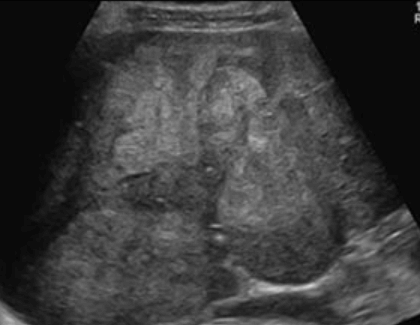

암부위와 정상조직의 경계가 뚜렷한 것을 말한다. 종양 내에 섬유성의 격벽이 존재하며 이것에 의해 소결절로 다시 구분된다. 간세포암의 초음파상은 직경 3cm 이상의 결절형이 특징적이며 저에코의 격벽과 경계가 되는 에코레벨이 다른 소결절이 모자이크 패턴(mosaic pattern)으로 관찰되며 피막에는 달무리(halo)가 존재한다.

2~3cm hcc sono features ③ 3~5 cm hcc sono finding

- hypo-hyperechoic

- heterogenous

- irregular

- hump sign (표면에 존재하는 결절형 종괴에서 간표면으로 종괴가 돌출하는 경우 나타난다)

- mosaic pattern (종양내부에 괴사나 출혈이 생겨 내부에 균열이 있는 것처럼 보이는 모자이크패턴이 나타남)

- color doppler : internal mass pattern (feeding artery)